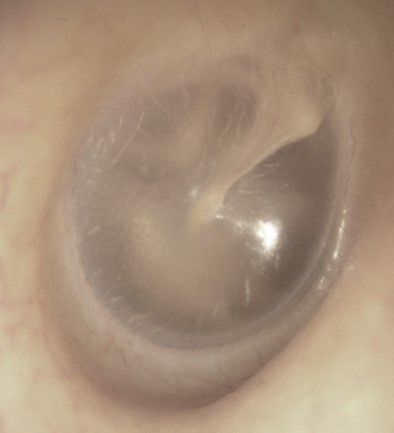

Voici votre examen otoscopique

Question 3: Votre examen clinique est en faveur

L’examen otoscopique et le contexte clinique sont en faveur d’une otite moyenne aiguë collectée.